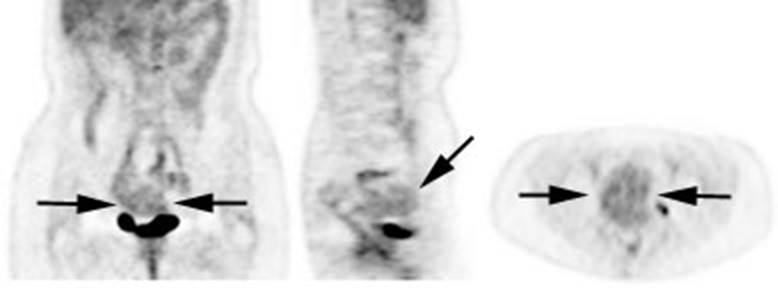

Figure 6 - Genitourinary activity: The image below

demonstrates activity within the collecting system of a transplanted kidney

(black arrows). This should not be mistaken for an abnormality.